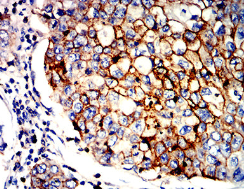

ITGB7 Mouse Monoclonal antibody[6A2G4]

Species Reactivity:    Human

Immunogen :   Purified recombinant fragment of human ITGB7 (AA: 20-174) expressed in E. Coli.

IHC    1/200 - 1/1000